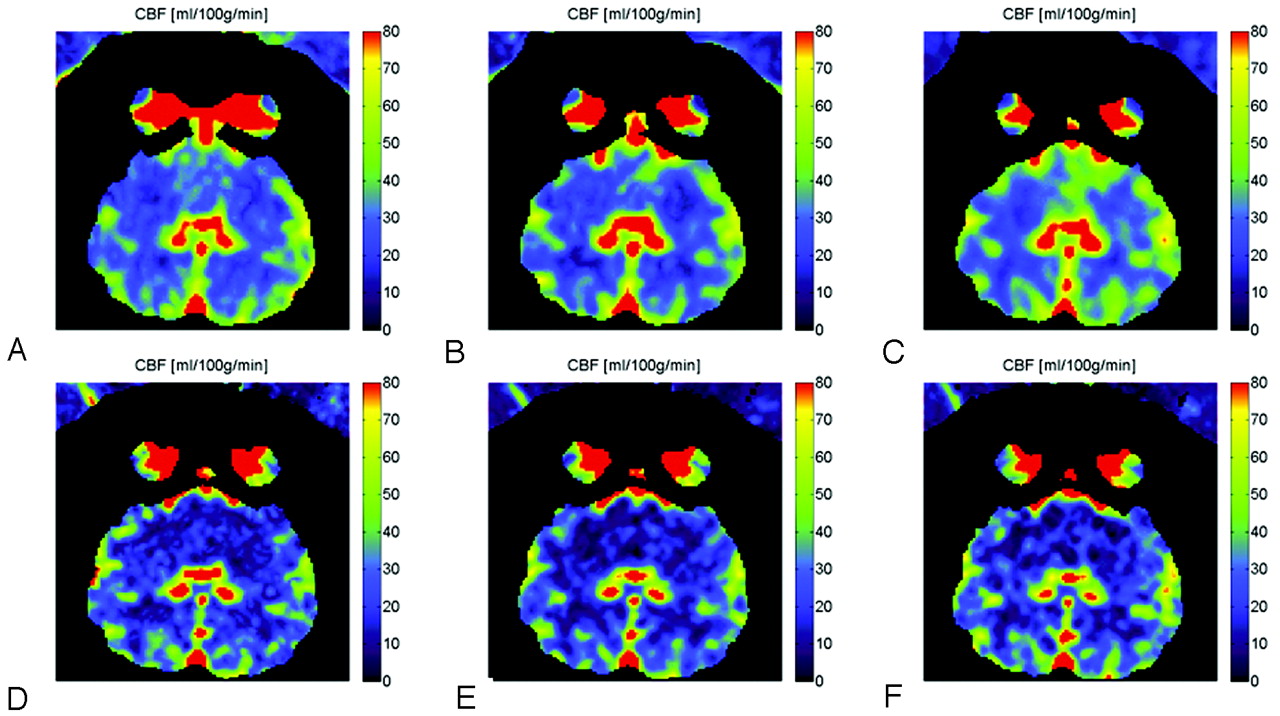

The representative CBF maps in 1 of the animals are shown in Fig 2. The results from different injections are compared between C-arm CBCT (top row) and clinical CT (bottom row). A qualitative analysis shows that the CBF values for the 2 imaging modalities have a similar range of values. The calculated CBF values from clinical CTP measurements ranged from 3.5 to 71.2 mL/100 g/min, with the average value ranging from 39.81 ± 11.96 to 49.80 ± 8.61 mL/100 mg/min for white matter and 13.43 ± 5.89 to 25.36 ± 14.47 mL/100 mg/min for gray matter. The lower values in the range were associated with the 6-mL/s 50% iodinated contrast injection, while the higher values were obtained for the 3-mL/s 67% iodinated contrast injection. There were significant effects of tissue type (P < .001) and injection method (P < .001). The average differences in the CBF values between the 2 hemispheres for gray and white matter, their SDs, and overall ρ and r values measured for the 3 injections for CT alone are shown in Table 1. Because the animals imaged were healthy adults, it is expected that the CBF values in the 2 hemispheres will have a close match. The highest correlation coefficients were obtained for the 6-mL/s 50% iodinated contrast injection.

CBF maps for 6-scan sets (A-B-C-D-E-F) from different injection-protocol C-arm CBCT (A−C) and CTP images (D−F). The 3 injection protocols used are 3 mL/s 67% (A and D), 6 mL/s 50% (B and E), and 3 mL/s 100% (C and F). All injections had a duration of 8 seconds.